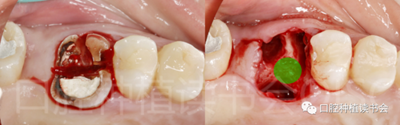

圖1 無法保留的上頜隱裂后牙,拔牙后即刻種植。

(5)可以有效的關(guān)閉拔牙創(chuàng)(圖2、圖3)。

圖2 初期穩(wěn)定性良好的位點(diǎn),采用愈合基臺(tái)+縫合固定的方法

關(guān)閉拔牙創(chuàng),術(shù)后1周獲得良好的軟組織愈合。

圖3 初期穩(wěn)定性不足的位點(diǎn),采用膠原蛋白覆蓋(倍菱)

+縫合固定的方法關(guān)閉拔牙創(chuàng),術(shù)后10天獲得良好的軟組織愈合。